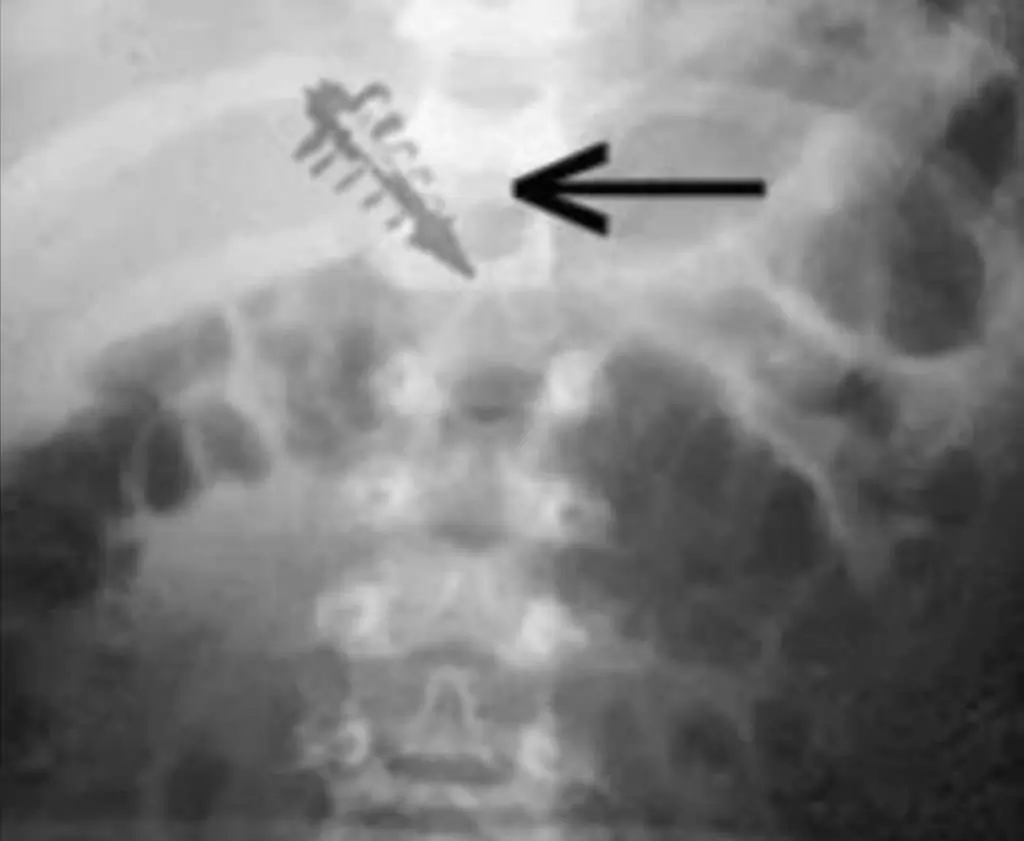

Jedan od najšokantnijih aspekata slučajeva koje je dr. Leir dokumentovao jeste apsolutno odsustvo vidljivih ožiljaka na pacijentima.

Logika nam nalaže da, ako je neki predmet veličine zrna riže ili vrha olovke umetnut duboko u tkivo, na koži mora postojati trag ulazne rane, šav ili bar diskoloracija kože.

Međutim, pacijenti dr. Leira su na rendgenskim snimcima jasno pokazivali prisustvo stranog metalnog tijela, dok je njihova koža iznad tog mjesta bila potpuno netaknuta.

Čak i pod jakim uveličanjem, integritet kože bio je savršen.